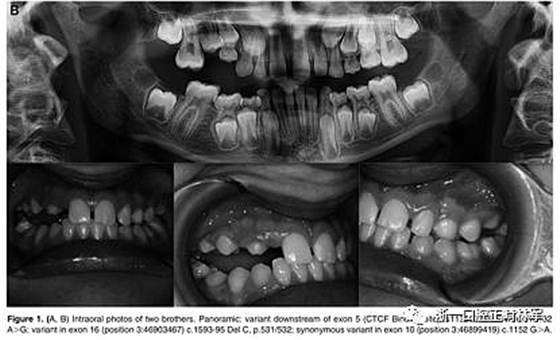

29例中有8例在PTH1R基因中发现杂合致病变异。表2显示了本研究中确定的突变概况。简言之,在8个受影响的受试者中有5个鉴定出三种错义突变,这些受试者以前没有根据与已发表的数据库的比较(表3)进行描述。在两个兄弟中鉴定出CTCF结合位点的变体(c.313×32 A.G rs113566258 SNP)(图1A,B)。

图1.(A,B)两兄弟的口内照片。全景:外显子5的下游变体(CTCF结合位点)rs113566258 SNPc.313±32A>G; 在外显子16中的变体(位置3:46903467)c.1593-95 Del C,p.531 / 532; 外显子10中的同义变体(位置3:46899419)c.1152 G>A.

兄弟姐妹被诊断为I型PFE并显示双边呈现。该变体(PTH1R基因的外显子5的下游c.313×32 A.G)发生在与转录因子相互作用的调节区中。除了这种突变之外,这些兄弟还受到第二个突变的影响,这些突变对每一个都是独特的:一个兄弟姐妹(II:1)也存在在外显子16的基因氨基末端发生的移码缺失,c.1593DelC ,第(Pro532Leufs *)(图1A,B)。

在另一个同胞(II:3)中,鉴定出在蛋白质氨基酸序列水平不引起变异的外显子,c.1152GA(rs200475872;图1A,B)中的同义变体,但涉及改变含氮碱。基于计算机分析,这种改变可能会影响mRNA的折叠并影响其半衰期和蛋白质生产。在这个患者样本中,在一个孤立的病例中发现了同样的同义变体c.1152G.A,由于PFE而具有严重的开合(图2)。

本研究中确定的低咬合的临床特征与PFE基于基因诊断和萌出障碍诊断标准的应用相一致。对特定相关牙科特征的仔细临床检查包括以下内容:至少一颗牙包括低咬合,局限于后部区域,单侧(38%;图1A)和双侧呈现(35%;图1B和2),至少有一个暂时性后牙(48%暂时;图1A,B和3A; 55%永久性,图3B)。

此外,观察到牙面特征如下:由于受影响侧的侧向开放咬伤的严重程度而引起的垂直骨骼不对称(35%;图1A,B和图3A,B);由下颌骨侧向偏离组成的面部不对称(图1A,B和图2;表4)。

这种不对称在单侧开合患者中更为明显。进一步发现受影响的患者与先前报道的患者存在上颌骨收缩和III类牙齿/骨骼关系(28%;图1A,B和图2)。至少有一例患者出现了相对于9名患者的低咬合。表4总结了PTH1R的表型结果和相关的突变分析(N = 8)。